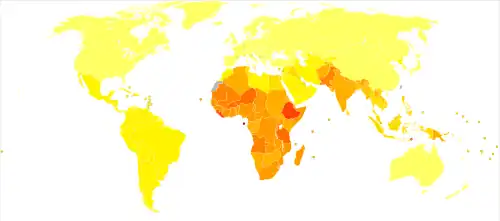

Epidemiology

| No data < 60 60–120 120–180 180–240 240–300 300–360 | 360–420 420–480 480–540 540–600 600–1000 > 1000 |

In 2008, it was estimated that 500 million people were infected with either syphilis, gonorrhea, chlamydia or trichomoniasis.[1] At least an additional 530 million people have genital herpes and 290 million women have human papillomavirus (HPV).[1] STIs other than HIV resulted in 142,000 deaths in 2013.[103] In the United States there were 19 million new cases of sexually transmitted infections in 2010.[104]

In 2010, 19 million new cases of sexually transmitted infections occurred in women in the United States.[5] A 2008 CDC study found that 25–40% of U.S. teenage girls has a sexually transmitted infection.[105][106] Out of a population of almost 295,270,000 people[107] there were 110 million new and existing cases of eight sexually transmitted infections.[108]

Over 400,000 sexually transmitted infections were reported in England in 2017, about the same as in 2016, but there were more than 20% increases in confirmed cases of gonorrhoea and syphilis. Since 2008 syphilis cases have risen by 148%, from 2,874 to 7,137, mostly among men who have sex with men. The number of first cases of genital warts in 2017 among girls aged 15–17 years was just 441, 90% less than in 2009 – attributed to the national HPV immunisation programme.[109]

AIDS is among the leading causes of death in present-day Sub-Saharan Africa.[110] HIV/AIDS is transmitted primarily via unprotected sexual intercourse. More than 1.1 million persons are living with HIV/AIDS in the United States,[111] and it disproportionately impacts African Americans.[112] Hepatitis B is also considered a sexually transmitted infection because it can be spread through sexual contact.[113] The highest rates are found in Asia and Africa and lower rates are in the Americas and Europe.[114] Approximately two billion people worldwide have been infected with the hepatitis B virus.[115]